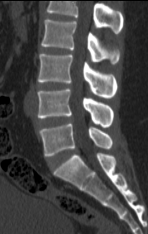

Chẩn đoán hình ảnh mô mềm tiên tiến cho vùng bụng.

Tăng cường độ tương phản I-ốt.

Đảm bảo hình ảnh chất lượng cao.